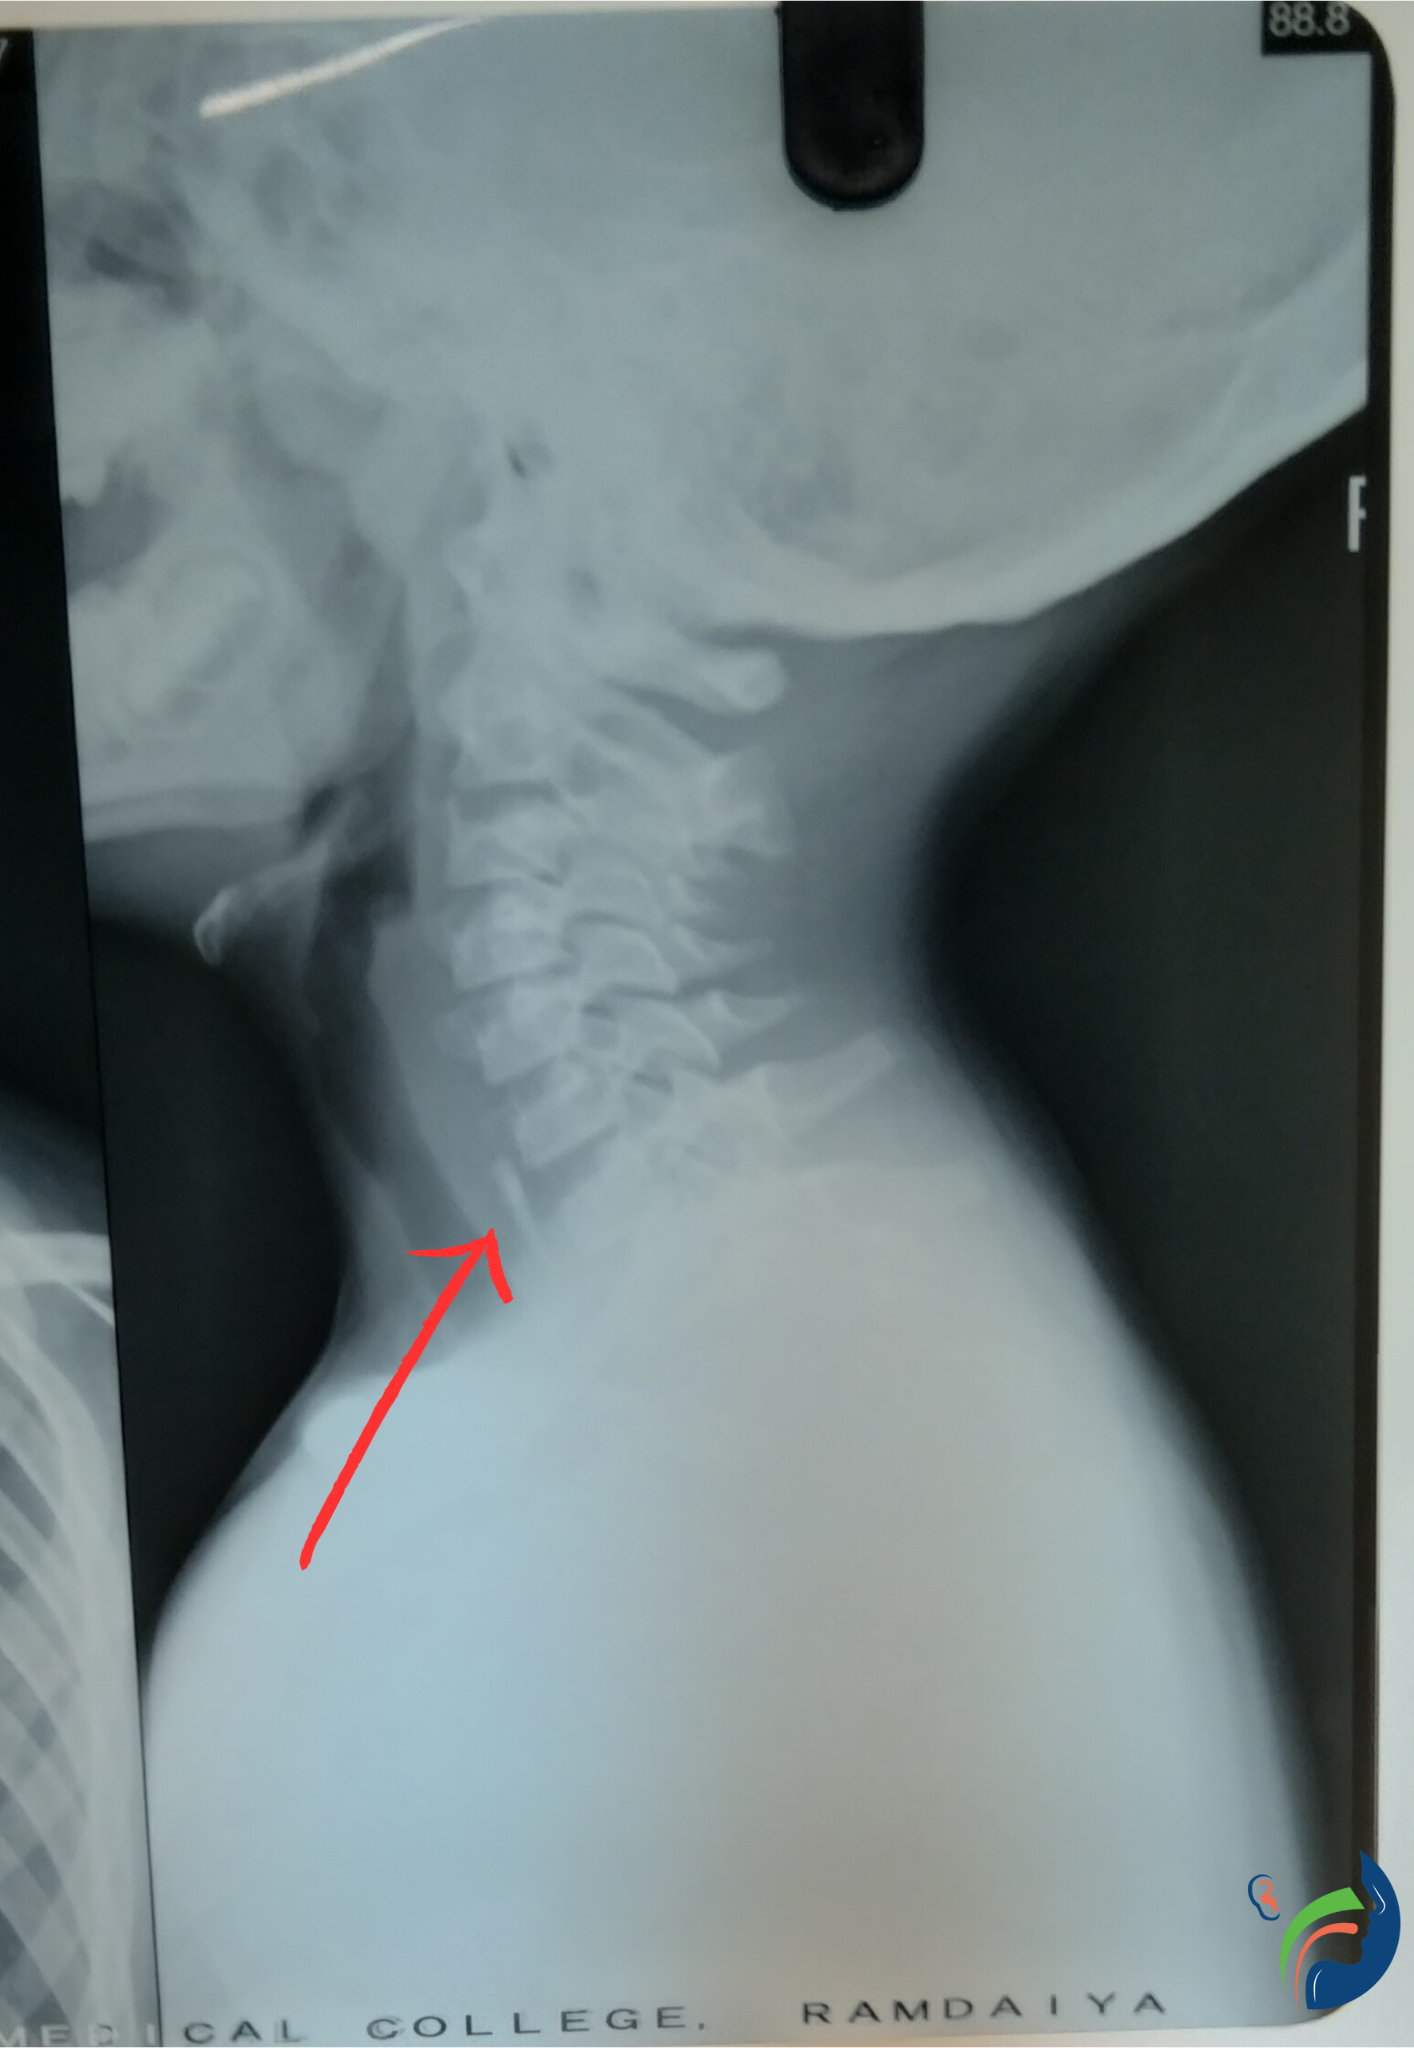

Esophageal foreign bodies are objects that become lodged in the esophagus, the tube that connects the mouth to the stomach. This can happen accidentally, such as when a child swallows a coin, or intentionally, such as when someone tries to swallow a large object, such as a piece of meat or a ball.